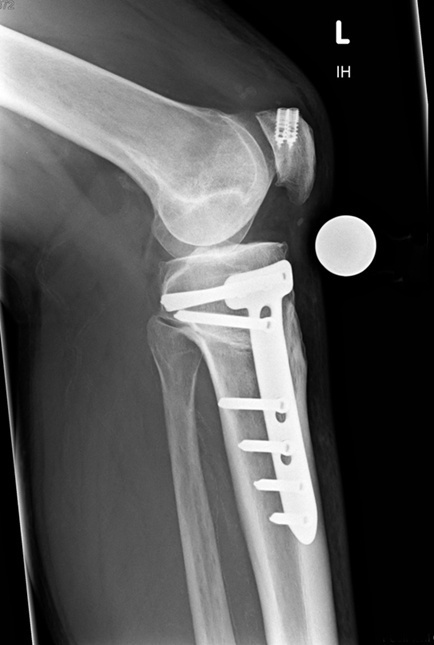

Dr. med. Alexander Strehl: Bei der häufigsten Umstellungsosteotomie am Unterschenkelkopf macht man einen Sägeschnitt am Knochen, klappt diesen gezielt auf und fixiert ihn mit einer winkelstabilen Platte; dies auf Basis dessen, was man vor der Operation bei der Planung gemessen und errechnet hat. Es entsteht ein winkelförmiger Spalt im Knochen, der von selber wieder zuwächst. Je nach Ort und Art der Deformität findet auch der Eingriff statt. Bei einem O-Bein ist dies meistens am Unterschenkelkopf. Es können aber auch Eingriffe am Oberschenkel nötig sein, vor allem beim X-Bein. Bei extremen Deformitäten kann auch eine Doppelosteotomie erforderlich sein, also dass man am Ober- und Unterschenkel korrigieren muss, um wieder eine gerade Achse zu erhalten. Dies muss man im Vorfeld genau analysieren und planen. Während der Operation wird die Beinachse mehrfach mit dem Ausrichtestab überprüft.

Dr. med. Alexander Strehl: Der Patient bleibt vier bis fünf Tage in der Klinik. Danach sind sechs Wochen Gehstöcke mit Teilbelastung angesagt. Wie stark der Patient mit den Stöcken belasten darf, hängt davon ab, wie stabil sich der Knochen während der Operation gezeigt hat und wie stark seine Beschwerden sind. Es folgt Physiotherapie, da es wichtig ist, dass das Gelenk gut beweglich bleibt. Nach sechs Wochen wird ohne Gehstöcke aufbelastet.

Die Platte kann grundsätzlich im Knie bleiben. Ich empfehle aber, sie irgendwann wieder rauszunehmen, auch da so eine allfällige später nötige Prothesenoperation einfacher ist.